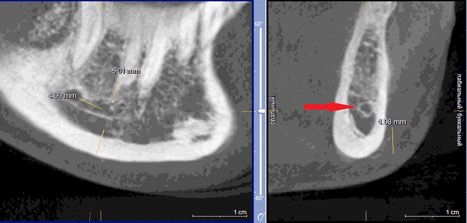

Данные осложнения происходят из-за повреждения резцовой петли – внутрикостного продолжения нижнелуночкого нерва (Рис. 1a и 1b), которая начинается от ментального отверстия и заканчивается индивидуально, как правило, на уровне латерального или центрального резца [1].

Рисунок 1а: КЛКТ. Панорамный реформат.

(Зеленая стрелка – резцовая петля, красная стрелка – подбородочное отверстие.)

Рисунок 1b: КЛКТ. Коронарный реформат нижней челюсти в переднем отделе.

(Зеленая стрелка – резцовая петля)